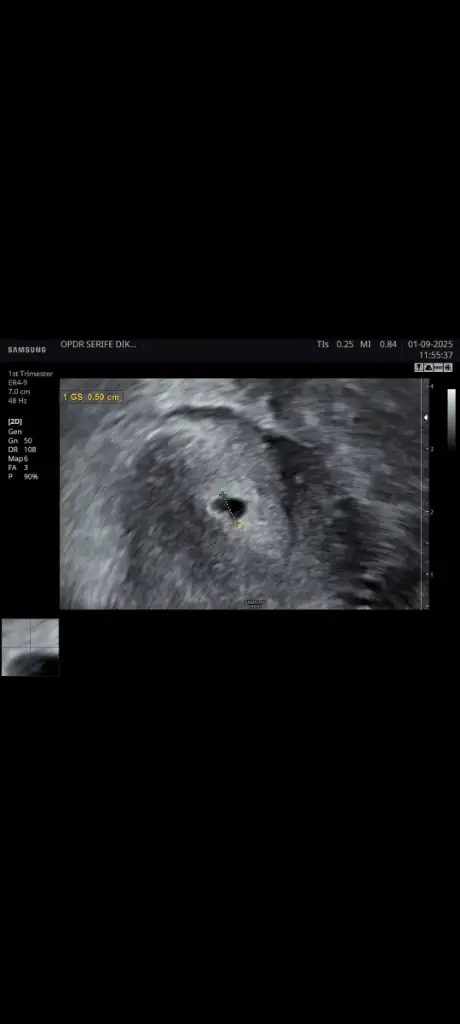

Hala kalp atışı yok ve kaç haftalık gebeyim onu bile bilmiyorum kalp atışı duyulmaması normalmi ultrason görüntüsüde ekliycem bilgisi olan varsa bana ne olduğunu anlatabilirmi

6 eylül de gittiğimde bana gelişimi yavaş ilaçları kes kendiliğinden vücut atsın dedi ama ben hala gelişim var diye biraz daha beklemek istedim yarın gene randevum var. Bana son adet tarihimden hesapladığını söyledi ama bu hesap yanlış diye biliyorum tüp bebek de embriyo transfer tarihinden hesaplanır diye biliyorum o yüzden biraz daha beklemek istedimDoktorun ne diyor